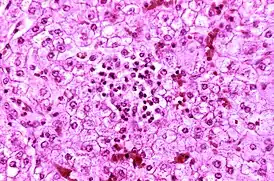

Синдро́м Ре́я, синдром Ре́йе (острая печёночная недостаточность и энцефалопатия, «белая печёночная болезнь») — редкое, но очень опасное, часто угрожающее жизни острое состояние, возникающее у детей и подростков (чаще в возрасте 4—12 лет) на фоне лечения лихорадки вирусного происхождения (грипп, корь, ветряная оспа) препаратами, содержащими ацетилсалициловую кислоту, и характеризующееся быстро прогрессирующей энцефалопатией (вследствие отёка головного мозга) и развитием жировой инфильтрации печени. Синдром Рея сопровождается гипераммониемией, повышением уровня АСТ, АЛТ в сыворотке крови (более чем в 3 раза) при нормальном уровне билирубина.

В основе синдрома Рея лежит генерализованное повреждение митохондрий вследствие ингибирования окислительного фосфорилирования и нарушения β-окисления жирных кислот.